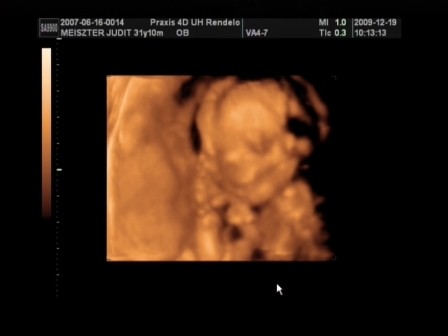

Minden rendben volt a 4D-n? Kislány vagy kisfiú?

nekem sajnos nem tudtak 4D-t készíteni, mert túl vastag volt a hasfalam! A lányokban már tudatosul, hogy testvérkéjük lesz?